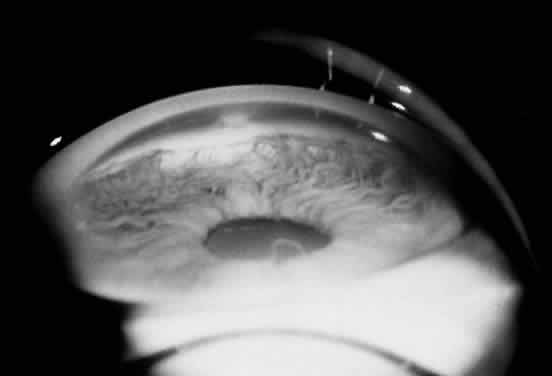

Ocular manifestations of the Axenfeld-Rieger syndrome include the presence of posterior embryotoxon and iris strands that attach to Schwalbe's line (Fig. 11). If the iris is normal, the condition is termed Axenfeld's anomaly. If iris defects are present, then it is classified as Rieger's anomaly. Iris findings in Rieger's anomaly may range from mild hypoplasia to full-thickness hole formation (Fig. 12). Glaucoma develops in approximately 50% to 60% of patients with Axenfeld-Rieger syndrome. When Rieger's anomaly is associated with systemic anomalies, it is known as Rieger's syndrome. Developmental abnormalities seen in Rieger's syndrome commonly affect the teeth and facial bones. These defects may include microdontia, hypodontia, and maxillary hypoplasia. Originally described as separate clinical entities, Axenfeld's and Rieger's anomaly are now considered to be variations in the spectrum of the same developmental disorder.

Fig. 11. Gonioscopic view of the iris processes in Axenfeld-Rieger syndrome. (Courtesy of James J. Reidy, MD)